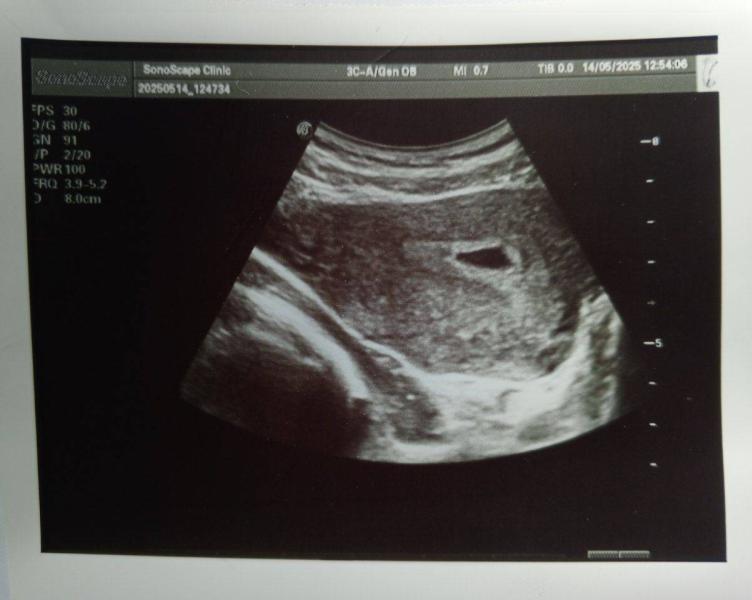

post image 1

Сказали, что эмбрион только начал появляться, поэтому записывать не стала, повторное узи в 6 и 7 недель.